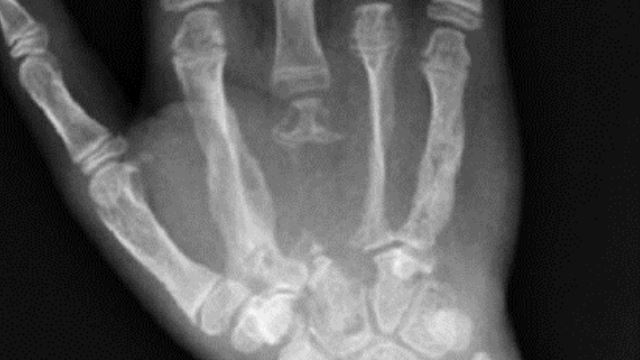

Doktor Kehairanan Tatkala Tulang Badan Hilang